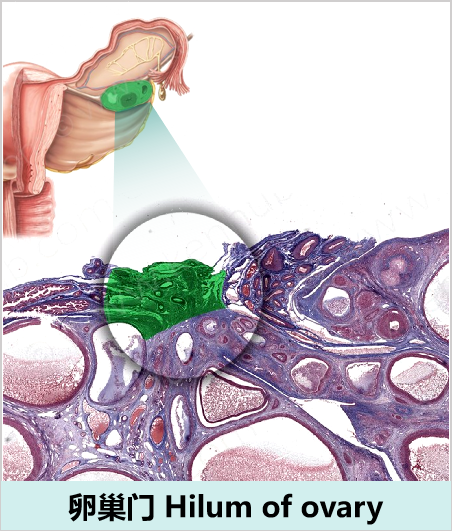

卵巢淋巴引流

自卵巢门发出输出淋巴管,卵巢淋巴引流的三大途径:

• 自卵巢门至腰淋巴结(上行途径):自卵巢门发出6~8条淋巴管,沿骨盆漏斗韧带与卵巢血管伴行上升,终止于第1、2腰椎水平的高位腹主动脉旁和肾静脉区域的腰淋巴结,为卵巢淋巴回流最主要途径。